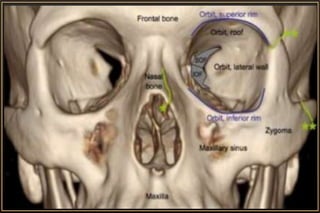

Anatomical Considerations

• Size, Shape & Relations

• 4 Walls, Base, Apex & Passages of Orbit

• Fascial Compartments / Surgical Spaces

• Contents & their Anatomy

• Paranasal Sinuses